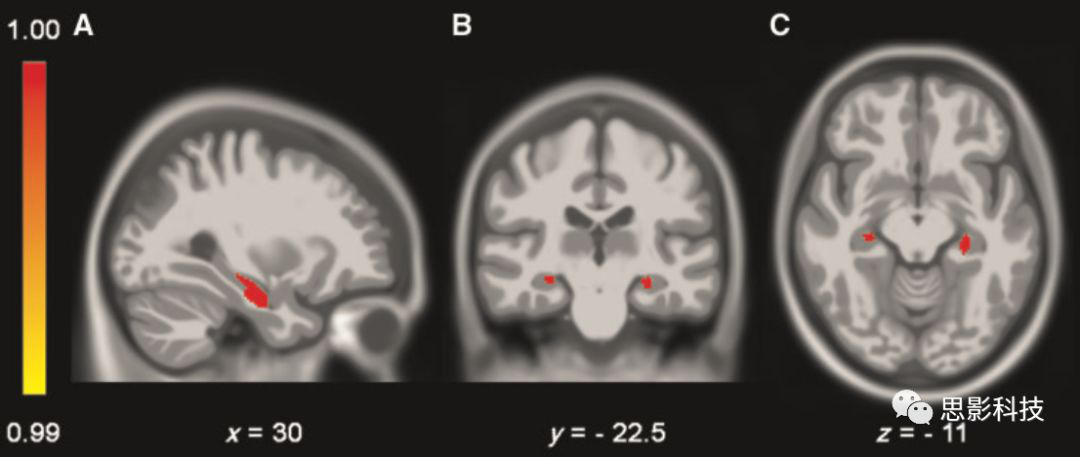

為探討海馬血管供應(yīng)模式是否影響海馬灰質(zhì)密度,研究者將單側(cè)海馬混合血管供應(yīng)被試、雙側(cè)海馬混合血管供應(yīng)被試分別與海馬單血管供應(yīng)模式被試進(jìn)行雙側(cè)海馬VBM分析比較。無論是單側(cè)還是雙側(cè)海馬混合血管供應(yīng)被試,他們雙側(cè)海馬灰質(zhì)密度均顯著高于海馬單血管供應(yīng)模式被試(表2)?;屹|(zhì)密度具有顯著差異的團(tuán)塊位于海馬前部區(qū)域,為脈絡(luò)膜前動脈分支供血(圖5)。而CSVD與非CSVD組間無顯著差異。2 VBM分析

5:海馬血管供應(yīng)模式相關(guān)的VBM分析??梢姾qR混合血管供應(yīng)模式的被試具有較高灰質(zhì)密度,主要位于海馬前部(P<0.001,未校正)。